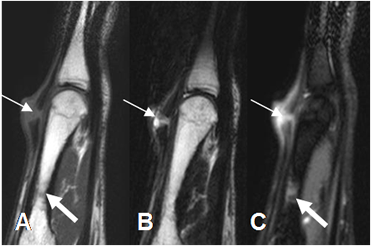

Fig 6. Laceración.

A: RM sagital en T1, B: RM sagital en T2 y C: RM sagital en STIR. Herida cortante en el dorso del 3º dedo, con solución de continuidad en el tendón extensor, por ruptura no retraída. Adicionalmente hay contusión en el tercio medio del metacarpiano. (Flecha gruesa).